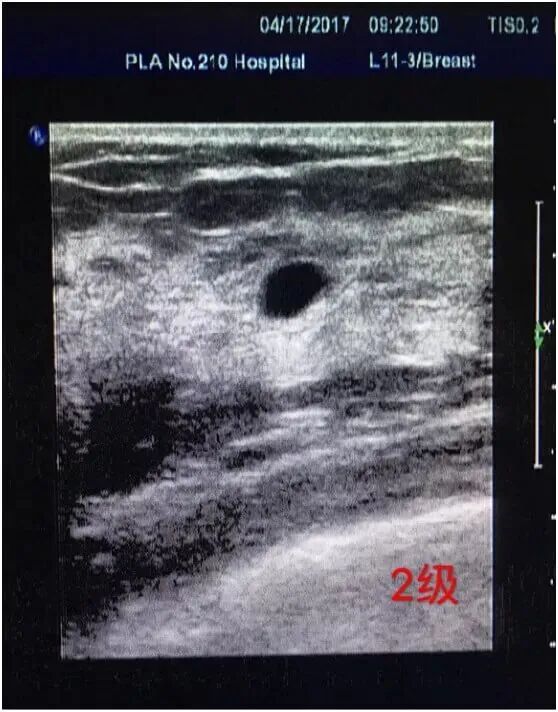

2 级

要是检查结果是2级,考虑良性病变的可能性比较大,建议定期来院复查,复查周期为每年一次。可以肯定的乳腺良性肿块(纤维脂肪腺瘤、脂肪瘤、单纯囊肿、积乳囊肿、积油囊肿)、肯定的良性钙化(如环状钙化、边界清楚的短条状钙化、粗的斑点状钙化、稀疏的大小较单一的圆点状钙化、新月形的沉积性钙化等)、多次复查超声检查图像变化不大的乳腺结节,手术后结构欠规则但多次复查图像无变化的、乳腺假体均属此类。如果发现结节较快速的增长,伴有疼痛以及其他不良反应,可以进行手术切除,之后进行病理检查。